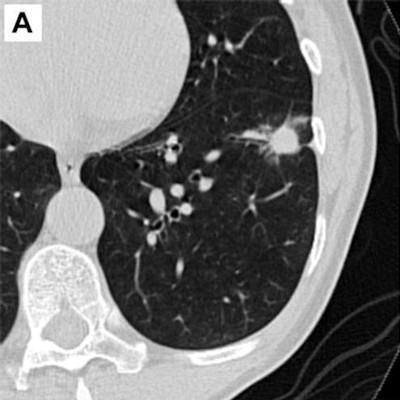

Study Shows 80% Long-Term Survival Results of Low Dose CT Lung Cancer Screening

A 20-year study conducted by the global I-ELCAP team confirms that low dose CT lung cancer screening has an outstanding 80% long-term survival rate. In those 20 years, I-ELCAP has supported around 90,000 lung screening participants, almost 300 publications and numerous international study confirmations. The I-ELCAP lung screening protocol represents a major advance in the war on cancer. To read more, visit https://www.auntminnie.com/index.aspx?sec=sup&sub=cto&pag=dis&ItemID=138686